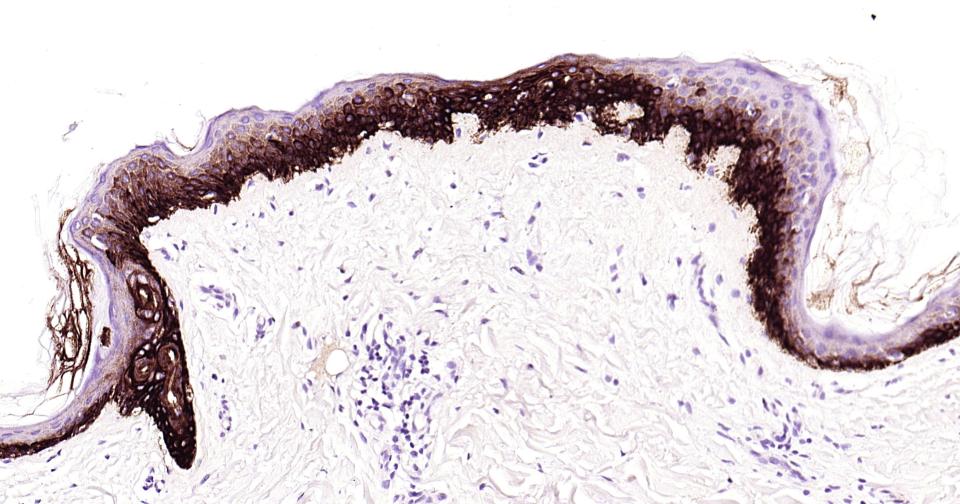

Paraformaldehyde-fixed, paraffin embedded Human Skin; Antigen retrieval by boiling in sodium citrate buffer (pH6.0) for 15 min; Antibody incubation with Cytokeratin 14? Monoclonal Antibody, Unconjugated(bsm-52054R) at 1:200 overnight at 4°C, followed by conjugation to the bs-0295G-HRP and DAB (C-0010) staining.